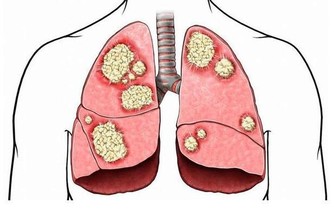

當一個人長期不出汗時,就會「中毒」,因為身體,尤其是血液裡的很多毒素廢物,不能全部經由大小便排出去,必須依靠出汗來排泄。中醫稱「汗為心之液」,來源於血,作為人體最深層廢物的血液垃圾,主要就是透過出汗──人體最表層的方式,直接排出體外。一個人要是不能正常地出汗,廢物混在血液裡排不掉,必然會搗亂作怪,而且可能打「游擊戰」—從一個臟腑,跑到另一個臟腑去,打一槍換一個地方,那就很難對付,會引起大麻煩。